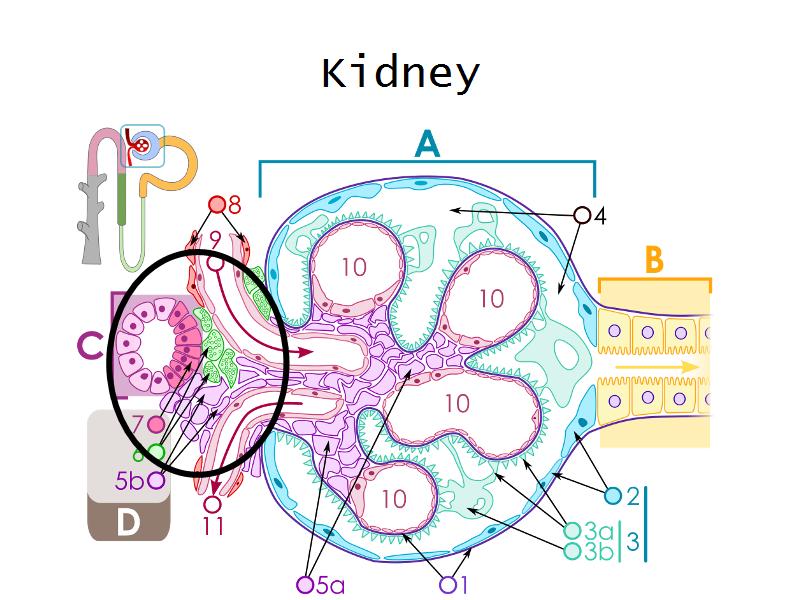

- Kidney

- Slide 76: Kidney